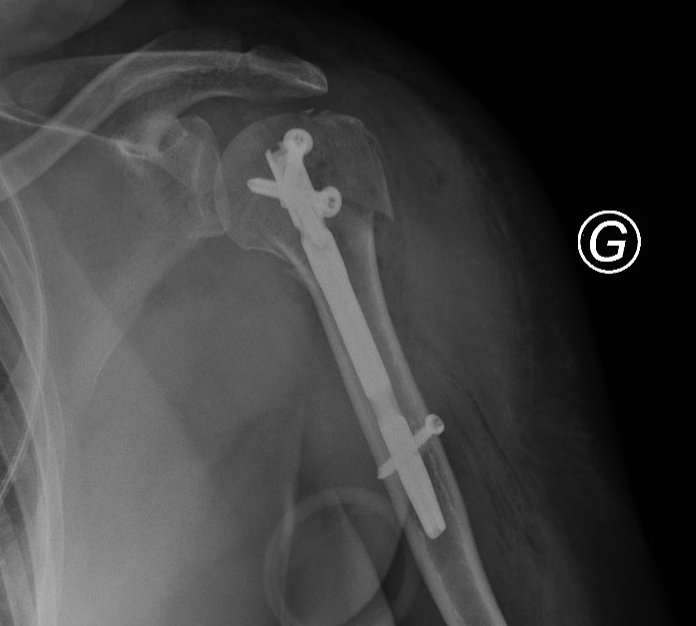

Intramedullary Nail Fixation

Intramedullary nail fixation is a surgical technique used to stabilise long bone fractures—most commonly of the humerus—by inserting a metal rod (nail) into the bone’s central canal.

The nail is secured with locking screws placed above and below the fracture to prevent rotation and shortening of the limb.

X-ray of a broken femur with surgical metal rod and screws for stabilization.